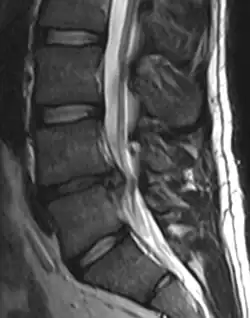

- Magnetic resonance imaging is the gold standard study for confirming a suspected LDH. With a diagnostic accuracy of 97%, it is the most sensitive study to visualize a herniated disc due to its significant ability in soft tissue visualization. MRI also has higher inter-observer reliability than other imaging modalities. It suggests disc herniation when it shows an increased T2-weighted signal at the posterior 10% of the disc. Degenerative disc diseases have shown a correlation with Modic type 1 changes. When evaluating for postoperative lumbar radiculopathies, the recommendation is that the MRI is performed with contrast unless otherwise contraindicated. MRI is more effective than CT in distinguishing inflammatory, malignant, or inflammatory etiologies of LDH. It is indicated relatively early in the course of evaluation (<8 weeks) when the patient presents with relative indications like significant pain, neurological motor deficits, and cauda equina syndrome. Diffusion tensor imaging is a type of MRI sequence used for detecting microstructural changes in the nerve root. It may be beneficial in understanding the changes that occur after herniated lumbar disc compresses a nerve root, and might help in differentiating the patients that need surgical intervention. In patients with a high suspicion of radiculopathy due to lumbar disc herniation, yet the MRI is equivocal or negative, nerve conduction studies are indicated.[44] T2-weighted images allow for clear visualization of protruded disc material in the spinal canal.

-

MRI scan of cervical disc herniation between C5 and C6 vertebrae -

MRI scan of cervical disc herniation between C6 and C7 vertebrae -

MRI scan of large herniation (on the right) of the disc between L4 and L5 vertebrae -

A rather severe herniation of the L4–L5 disc -

Example of a herniated disc at L5–S1 in the lumbar spine